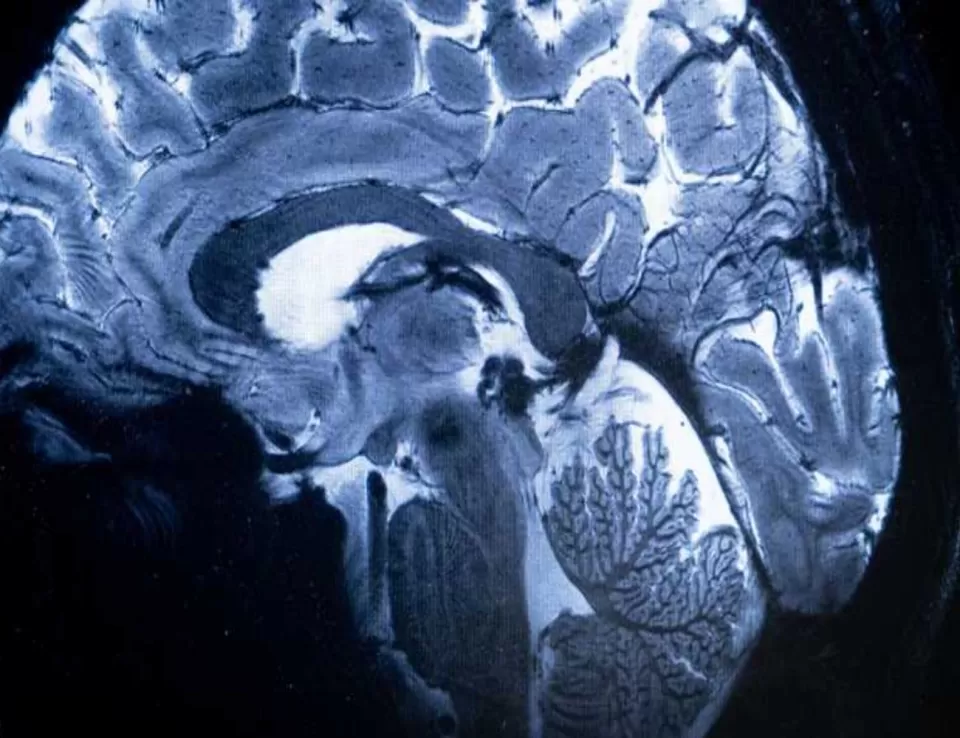

وأظهرت عمليات مسح التصوير بالرنين المغناطيسي لـ30 مريضا أدخلوا المستشفى بسبب "كوفيد 19" في وقت مبكر من الوباء قبل نشر اللقاحات، علامات على التهاب في جذع الدماغ، وهو جزء صغير لكنه بالغ الأهمية لأنه يتحكم بوظائف الجسم التي تدعم الحياة، مثل التنفس والنبض وحركة الدم، وتشير عمليات المسح إلى أن الإصابات الشديدة بفيروس كورونا يمكن أن تثير رد فعل مناعيا يؤدي إلى التهاب جذع الدماغ، مما يسبب أعراضا يمكن أن تستمر لأشهر بعد خروج المرضى من المستشفى، وذلك حسب الدراسة المنشورة في صحيفة "برين" العلمية.

واستخدمت روا وزملاؤها أجهزة تصوير بالرنين المغناطيسي قوية لفحص أدمغة المرضى، وكشفت هذه الأجهزة عن تفاصيل كافية لرؤية الالتهابات والتشوهات الدقيقة في أنسجة جذع الدماغ، علما أن جميع المرضى أدخلوا إلى المستشفى بسبب إصابات شديدة بفيروس كورونا قرب بداية الوباء.

وسلطت الفحوصات الضوء على التشوهات المرتبطة بالالتهاب في أجزاء متعددة من جذع الدماغ، التي ظهرت بعد أسابيع من دخول المرضى إلى المستشفى، وكان الضرر لا يزال واضحا في عمليات المسح بعد أكثر من 6 أشهر.